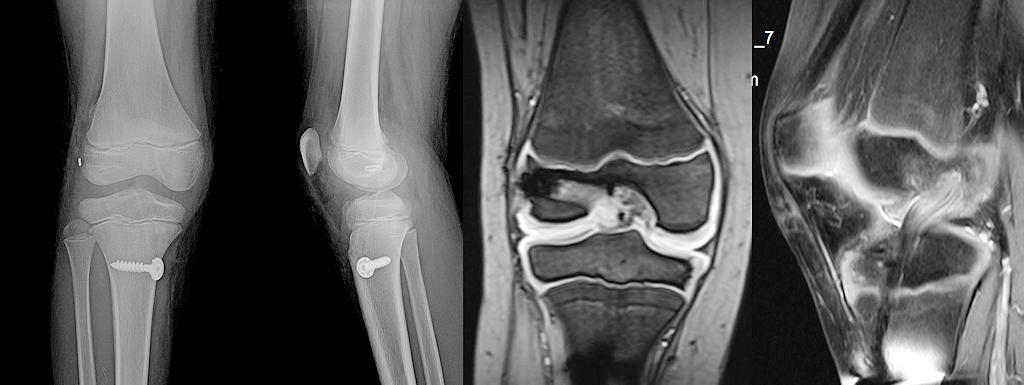

Ön çapraz bağ cerrahisi yapılan çocuklar büyüme tamamlanana kadar düzenli aralıklarla kontrol edilmelidir (Resim 4). Yıllık röntgenler ile bacak boyları arasında eşitsizlik veya açısal şekil bozukluğu olup olmadığı takip edilir. Erişkinlerin aksine, çocuklarda cerrahiden bir yıl sonra diz çevresindeki implantların çıkartılması önerilir.

Çocuk ve ergenlerde yapılan ön çapraz bağ cerrahileri ile hastaların %90’ından fazlasında başarılı sonuçlar elde edilebilir. Eşlik edebilecek kıkırdak ve menisküs yaralanmalarına da aynı cerrahi sırasında onarım yapılmalıdır. Ameliyat sonrasında 3-4 haftalık bir koltuk değneği kullanımı gerekli olur. Diz rehabilitasyonu ameliyattan hemen sonra başlar. Spora dönüş 9 aydan önce olmamalıdır (Resim 5). Yirmi yaşın altında ve futbol/basketbol gibi darbeli sporlara dönen hastalarda %10-15 tekrar yaralanma riski, % 5 oranında karşı dizde ön çapraz bağ yaralanması riski olduğu akılda tutulmalıdır.